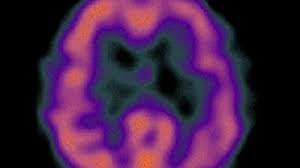

Cauzele bolii alzheimer nu sunt complet elucidate, deşi sunt cunoscute modificãrile care apar în creierul persoanelor afectate. Boala alzheimer este o afectiune degenerativa primara cu disfunctie generala difuza permanenta, durabila si ireversibila.

Cauzele bolii alzheimer nu sunt complet elucidate, deşi sunt cunoscute modificãrile care apar în creierul persoanelor afectate. De asemenea, boala alzheimer este clasificata in functie de varsta la care apare, si anume boala cu debut timpuriu pana in varsta de 65 ani. Boala alzheimer este o boala progresiva, incurabila, care distruge treptat celulele neuronale iar pacientii afectati incep sa aiba probleme de memorie.

Alzheimer este o afectiune neurologica care determina moartea unor celule de la nivelul creierului, care are ca si consecinta pierderile de memorie si declinul cognitiv.

Boala alzheimer nu se întâmplã peste noapte. Boala alzheimer este o boală degenerativă a creierului, afectând memoria, limbajul, comportamentul, capacitatea de judecată și inteligența. Alzheimer este un tip de dementa care debuteaza cu simptome blande si evolueaza treptat.